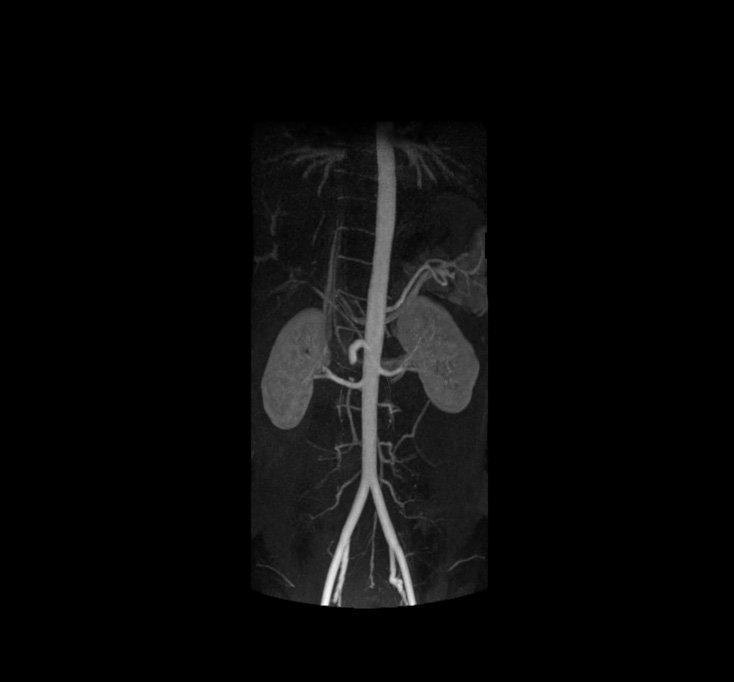

MRI Aorta